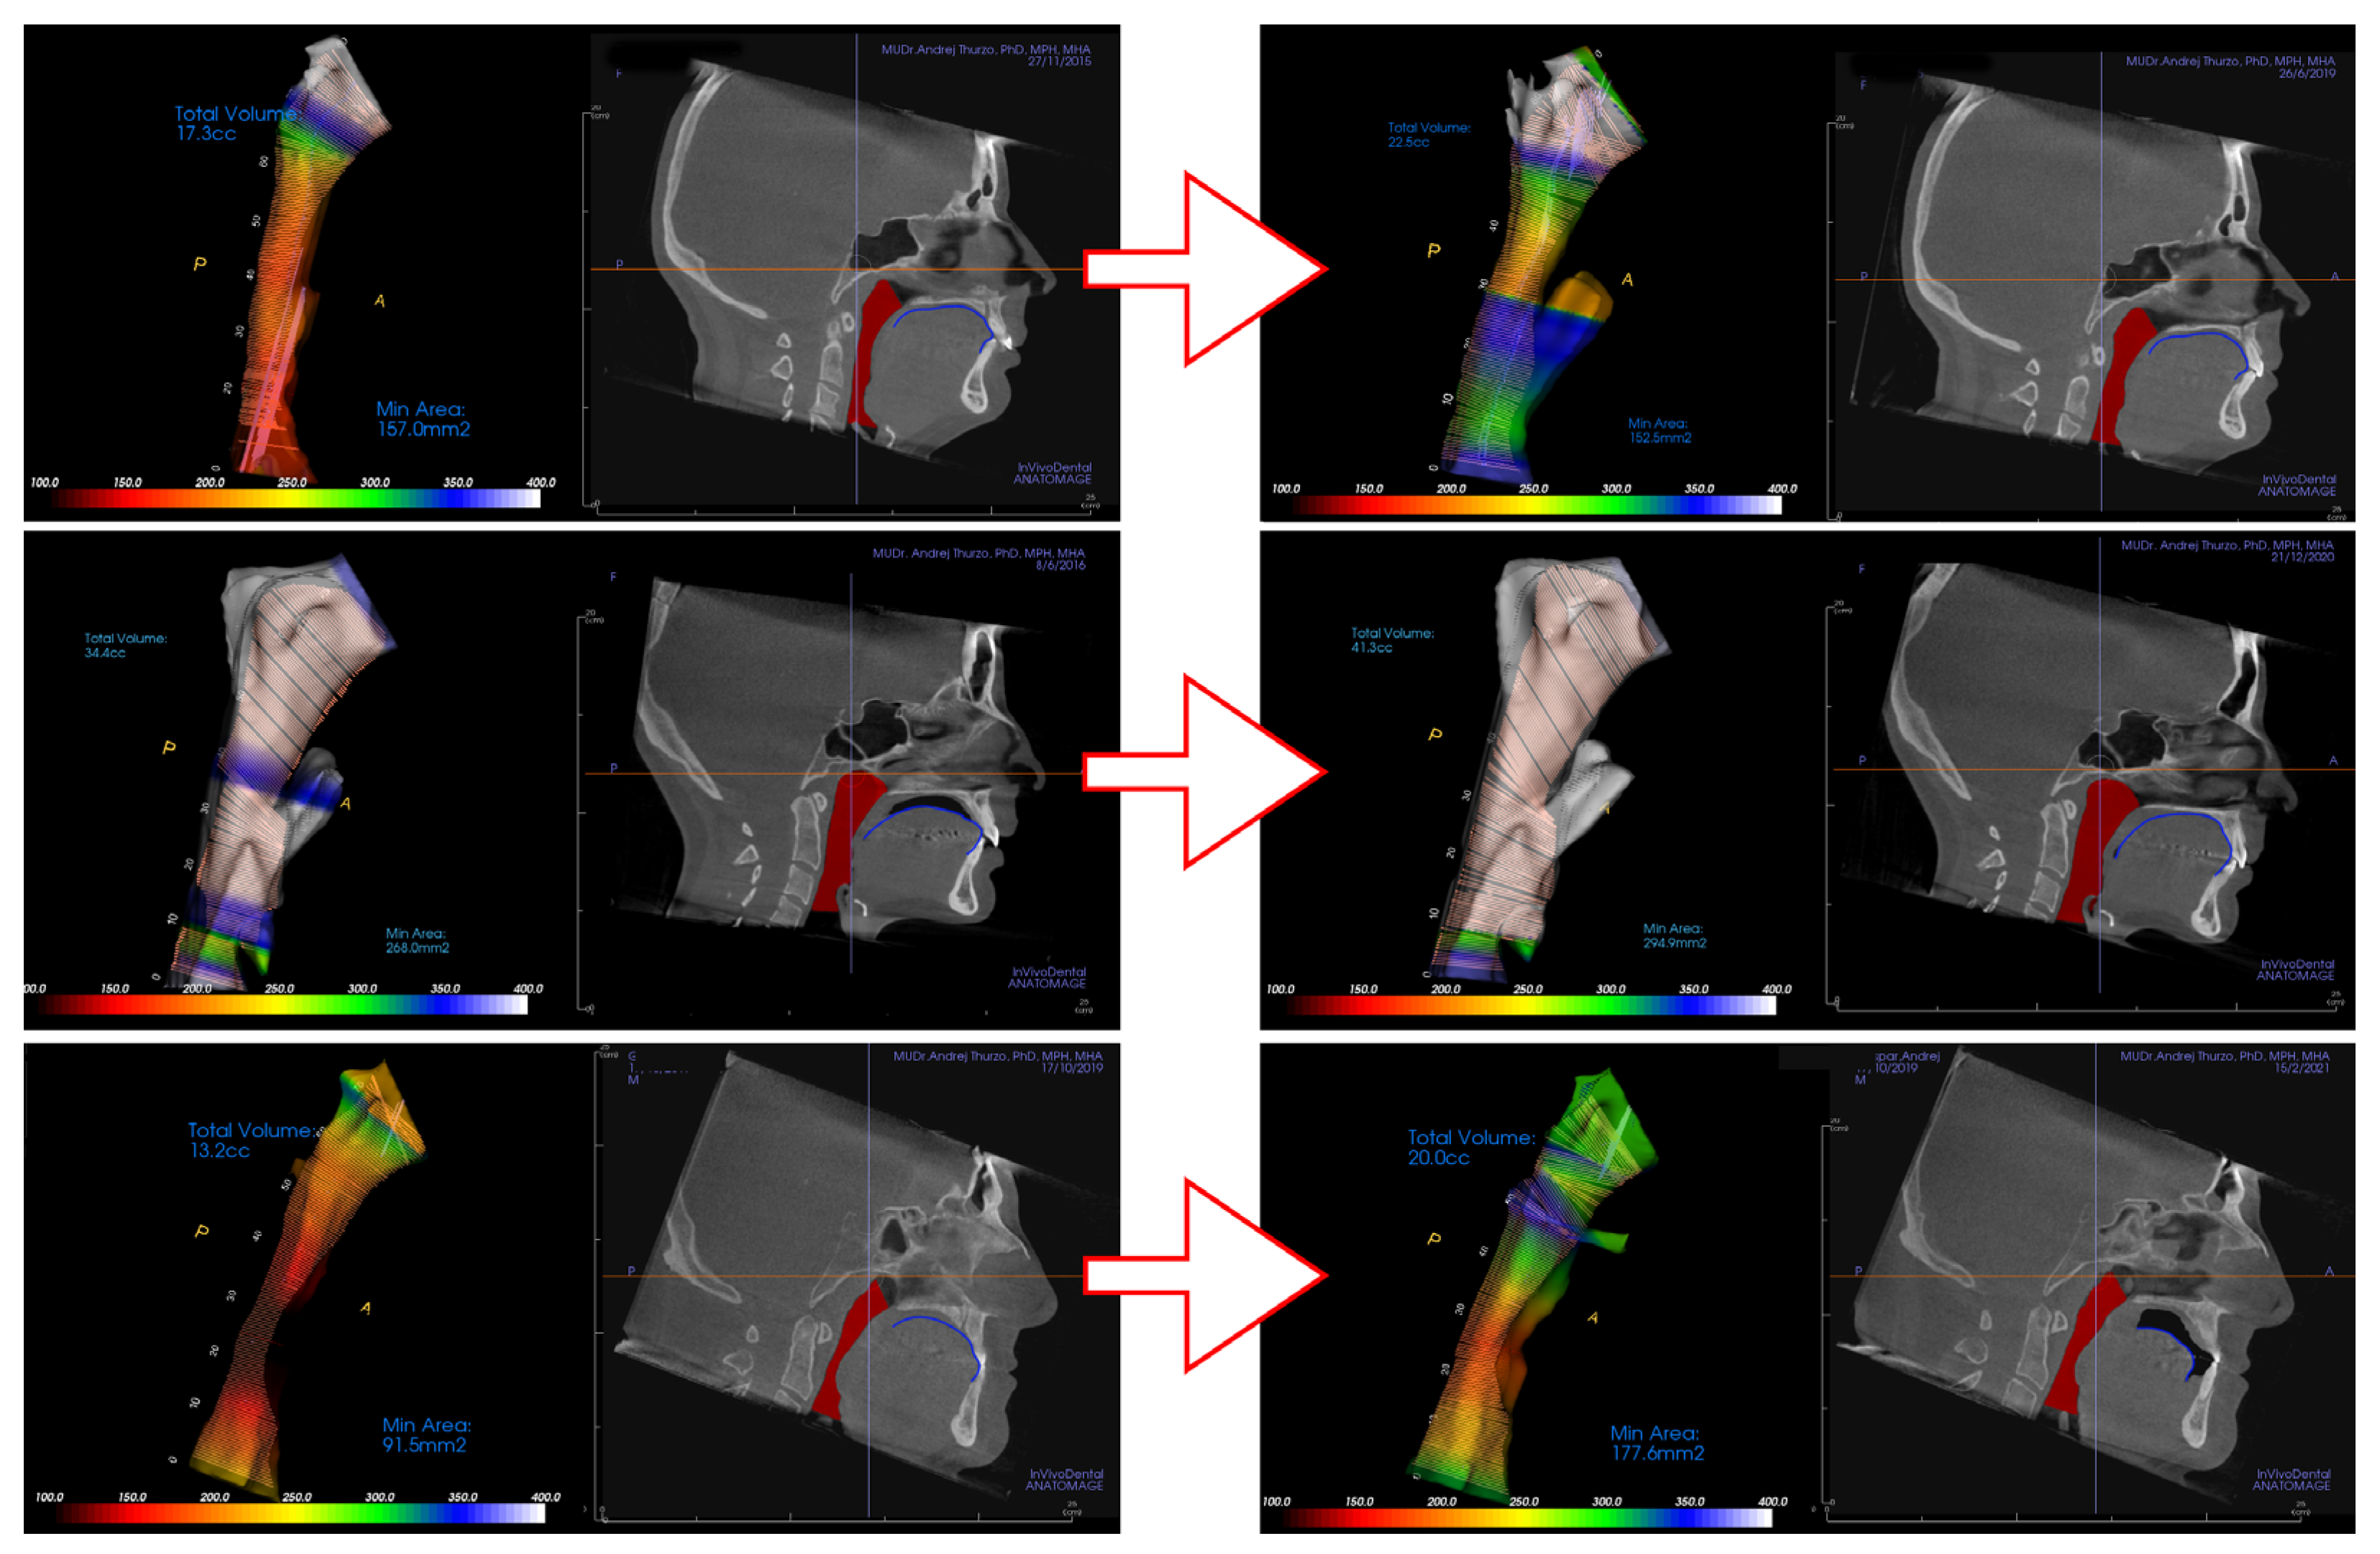

Example of the software 3D evaluation of the airway from the CBCT shows pre-treatment airway constriction (Figure 3a) and post-treatment evaluation after orthodontic therapy (Figure 3b). This example shows rather insignificant improvement of airway constriction as well no significant change of tongue posture (blue).

In this study, two independent clinicians evaluated changes of the tongue position in CBCT lateral view in relationship to the surrounding oral cavity. Evaluation of the change of the tongue position in the oral cavity was binary (Yes/No). The upper contour of the dorsum linguae was identified (Figure 4) and compared between initial and final scans. Only significant changes of the contour of dorsum linguae were evaluated as “different posture”. The clinicians were unable to recognize if the recorded position from the final CBCT was the true relaxed position of the patient’s tongue or just a temporary situation during final CBCT scanning.

Various clinical situations were evaluated. In situations where the contour of the dorsum linguae could not be differentiated from surrounding soft tissues it was considered in continuous contact. If such continuous contact was on the initial and as well final CBCT scan, tongue position in oral cavity was evaluated as unchanged, although the treatment could have changed teeth positions in the alveoli, and thus oral cavity shape and physical borders for tongue could have changed (Figure 4 top). Figure 4 shows three distinct examples of clinical situations where a not necessarily worsened position of tongue posture results in worsening of airway constriction (Figure 4 below), and post-treatment change of tongue position in the oral cavity (Figure 4 middle) improving an even previously unconstructed airway.

Figure 4. Various clinical situations in airway and tongue position in the oral cavity shown from the top. (1) Initially constricted airway ending in unconstricted setup with the tongue in connection with the upper palate and incisors with obvious change of lower incisors position. (2) In the middle is shown the situation of patient from control group with permanently unconstricted airway with changed tongue position. (3) Example on the bottom shows improvement in the airway clearance despite tongue position in the oral cavity being posterior in comparison to initial CBCT.